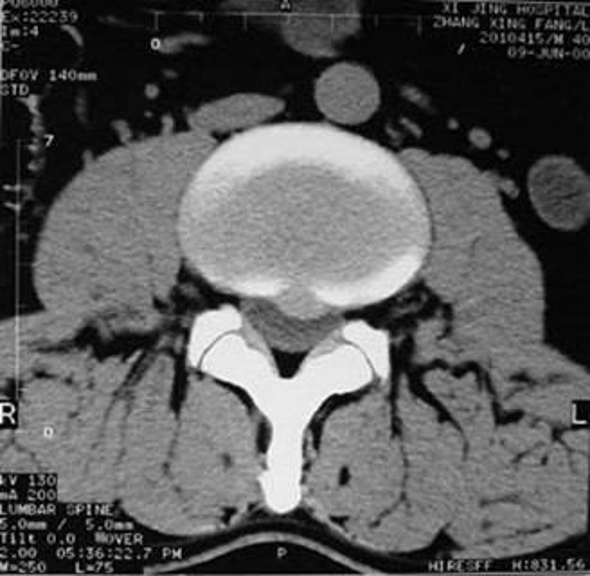

椎间盘突出症分类与微创方法的选择

1、椎间盘膨出(高压力):化学溶核类、机械减压类

2、椎间盘突出(高压力):机械减压类、化学溶核类、靶点治疗类、机械摘除类

3、椎间盘脱出 低压力:机械摘除类

4、椎间盘空洞 低压力:靶点治疗类、纤维环成形术